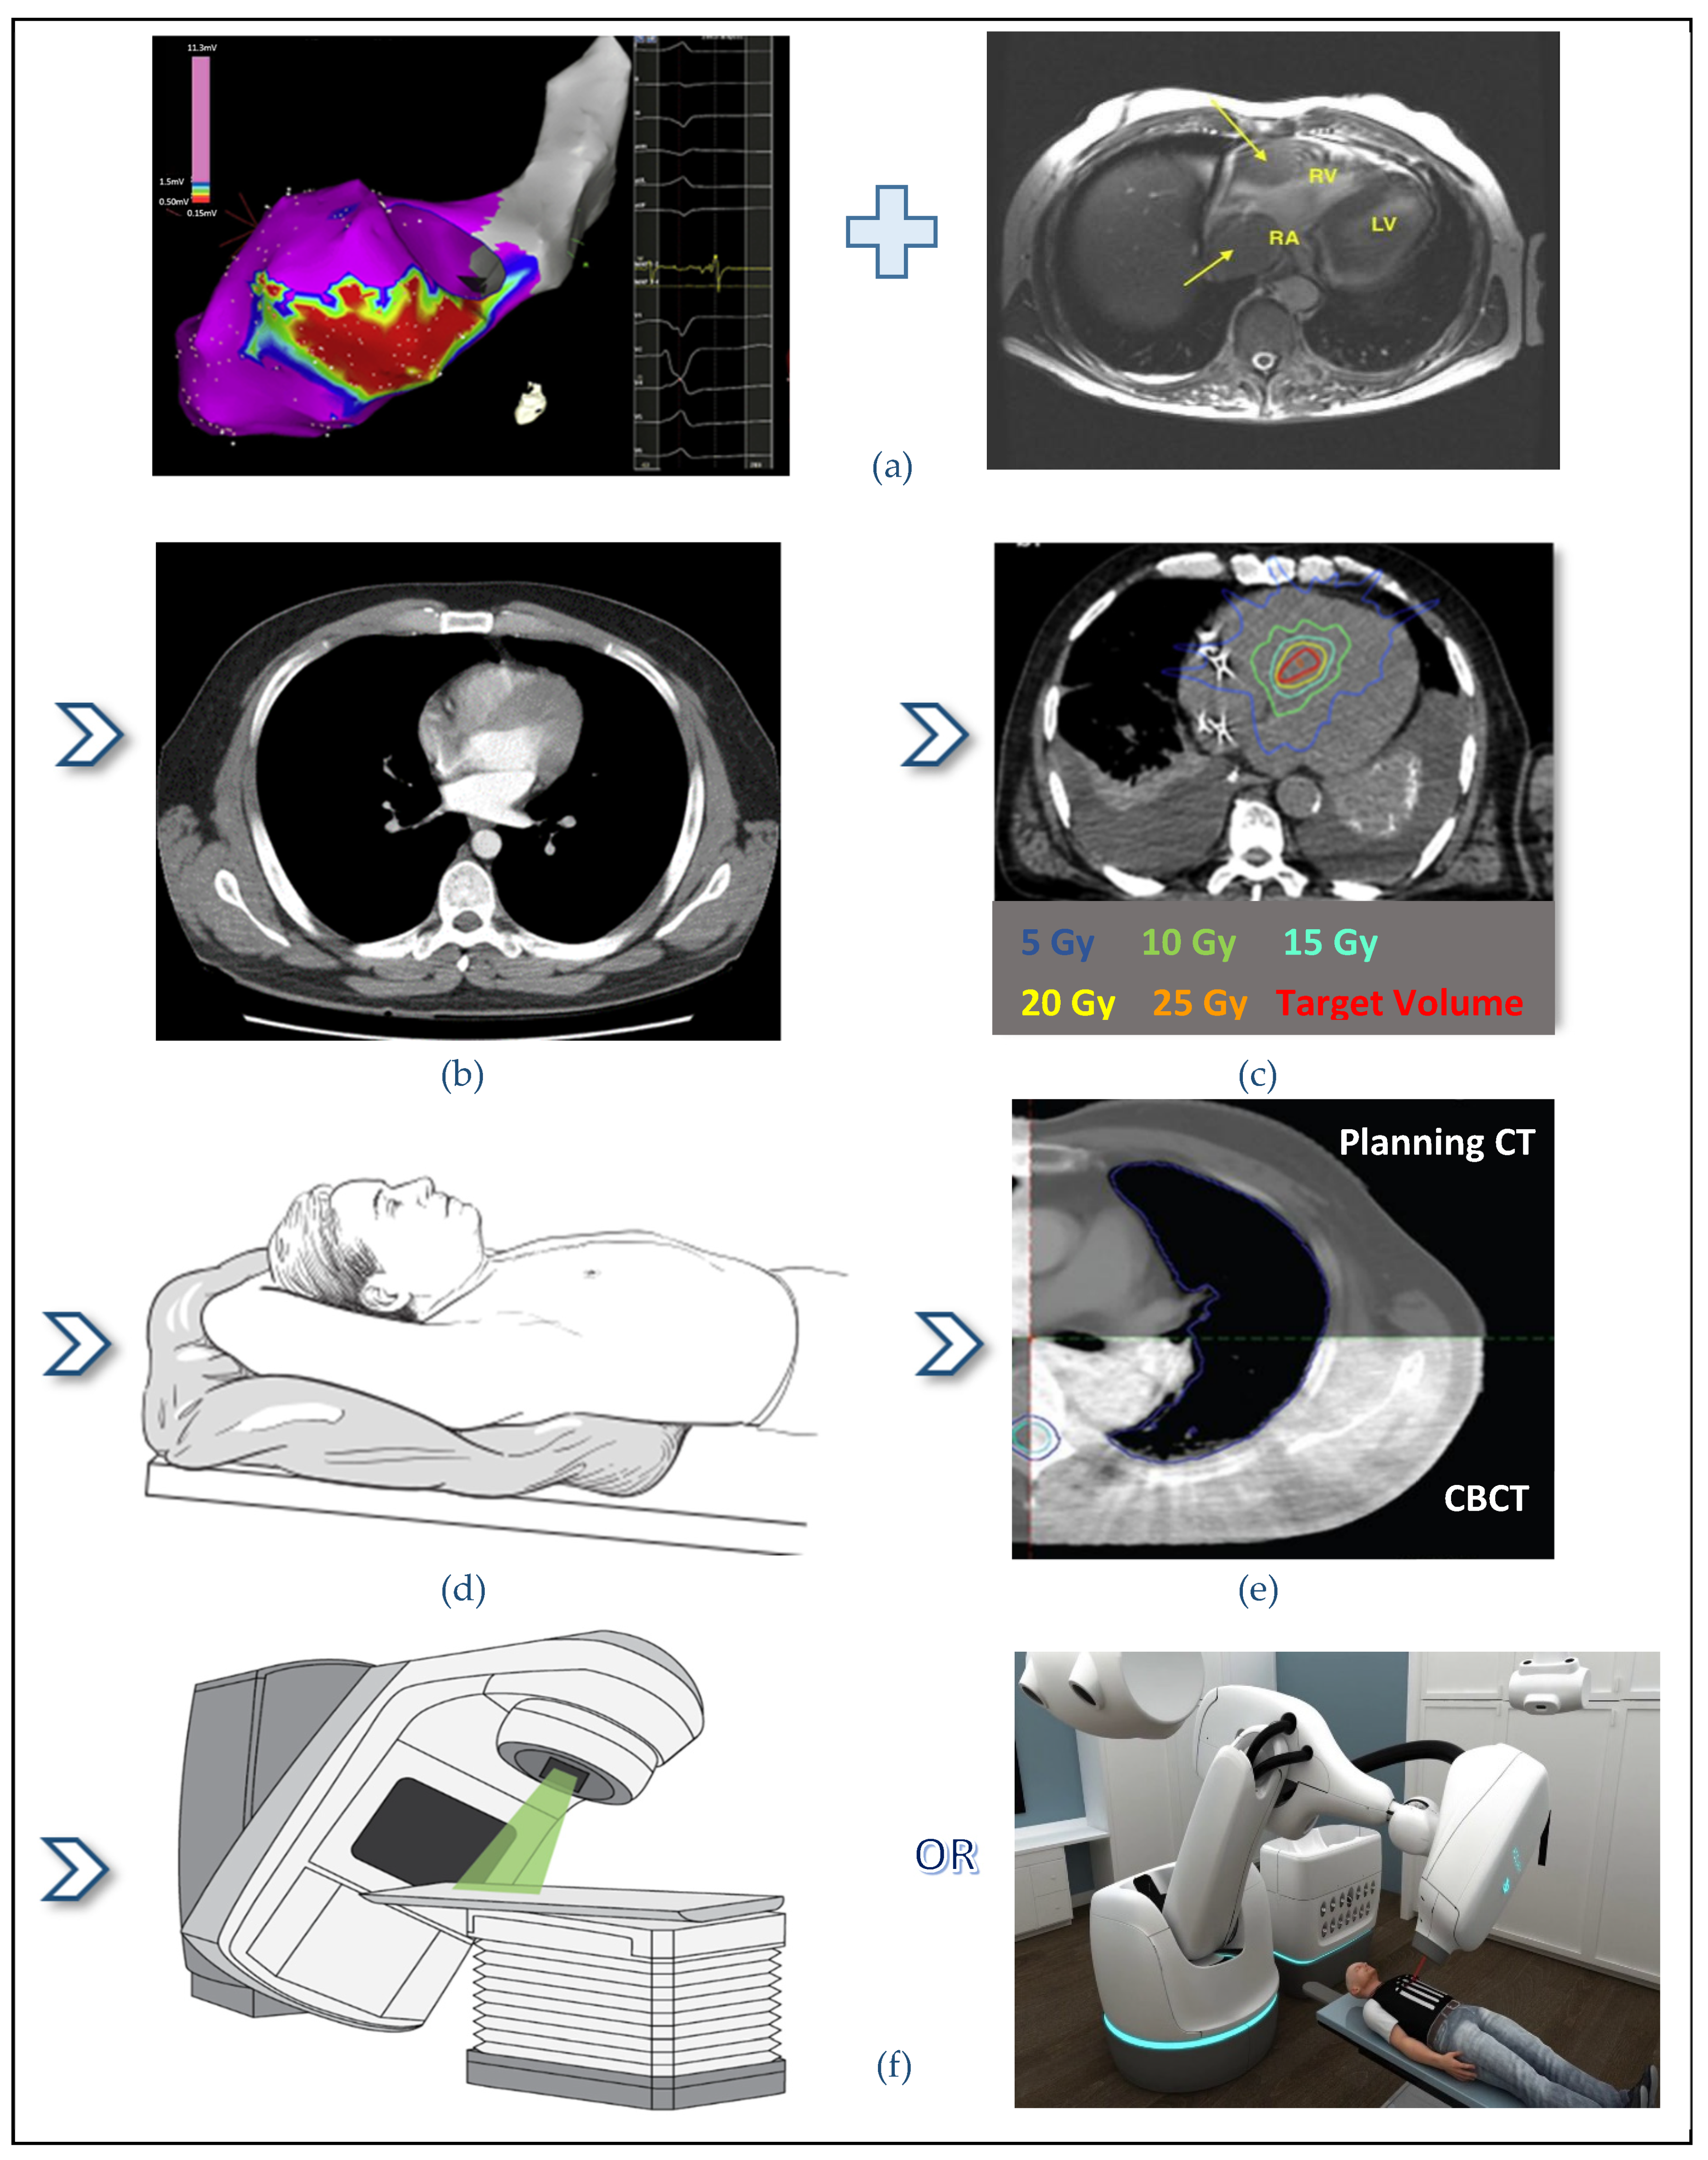

2.3. STAR Workflow and Treatment Delivery

2.3.2. Imaging the Arrhythmia Substrate

2.3.3. CT-Simulation

2.3.4. Interfraction Motion Management

2.3.8. Treatment Delivery